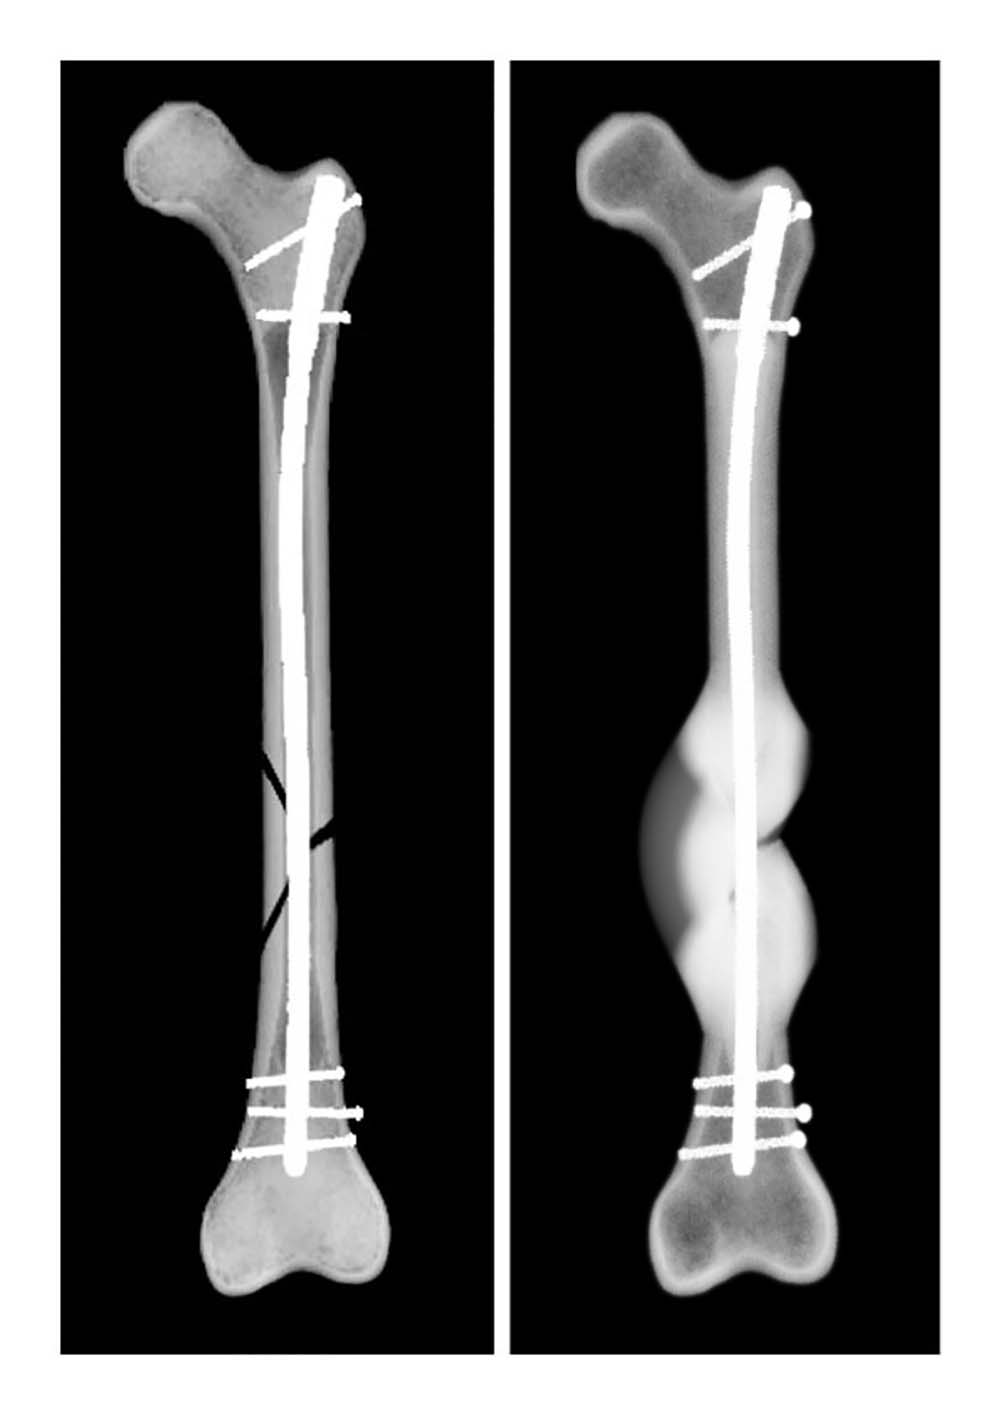

Für die Simulation wurden die klinischen Daten von 36 Patient*innen rückblickend analysiert. Diese hatten sich einen Schaftbruch des Oberschenkelknochens zugezogen, der durch die Implantation von Marknägeln versorgt worden war. Mithilfe von postoperativen Daten konnte die Computersimulation das Heilungsergebnis von 30 Fällen korrekt vorhersagen. „Bisherige Studien zum Ulmer Frakturheilungsmodell basierten auf Daten aus Tierversuchen oder aus Versuchen unter Laborbedingungen. Die Kooperation mit dem UKU hat es uns nun ermöglicht, das Heilungsmodell erstmalig mit klinischen Daten zu testen. So konnten wir den Prototypen des Softwaretools weiterentwickeln“, sagt Dr. Lucas Engelhardt von OSORA. „Das Heilungsmodell ist nicht nur in der Lage, Informationen zu erfolgreichen Heilungsverläufen zu generieren. Es wird ebenso zukünftig möglich sein, das Risiko für Komplikationen bis hin zu Pseudoarthrosen – also knöchernen Fehlheilungen – zu kalkulieren“, ergänzt Dr. Frank Niemeyer, ebenfalls von OSORA. Unter Berücksichtigung von patientenindividuellen Parametern, wie Größe und Gewicht, und Begleiterkrankungen, wie Osteoporose oder Adipositas, können dann Behandlungswege für jeden Patienten und jede Patientin individuell erstellt werden. Die Simulation unterstützt so die ärztliche Expertise durch Informationen zur Belastungsfähigkeit des Knochens während der Heilung.

Lediglich in sechs Fällen – von denen zwei Knochenbrüche geheilt und vier nicht geheilt waren – war die Prognose der Computersimulation nicht korrekt. „Jeder Patient heilt anders, jede Fraktur hat ihre Besonderheiten. Wir können aus den Daten ableiten, warum die Simulation in diesen Fällen nicht den realen Frakturheilungsverlauf abbildet, um neben der Biomechanik weitere Einflüsse auf das Knochenwachstum im Modell mit zu berücksichtigen. Diese Informationen sind für die weitere Entwicklung unserer Softwareplattform von größter Bedeutung, um die Präzision der Vorhersage kontinuierlich zu erhöhen“, erklärt Dr. Lucas Engelhardt.

„Die chirurgische Versorgung von Frakturen durch Osteosynthese – also die operative Verbindung von zwei oder mehr Knochen oder Knochenfragmenten – ist ein elementarer Baustein in der Therapie unserer Patienten. Je früher Einflussfaktoren erkannt werden, die den Heilungserfolg gefährden, desto mehr Spielraum hat der behandelnde Arzt für Anpassungen des Therapieplans. Mit der biomechanischen Analyse und Simulation des Heilungsverlaufs kann zukünftig ein weiteres Hilfsmittel die Behandlungsmöglichkeiten ergänzen und Ärztinnen und Ärzte unterstützen“, so PD. Dr. med. Konrad Schütze, Oberarzt an der Klinik für Unfall-, Hand-, Plastische und Wiederherstellungschirurgie.